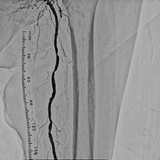

この装置では循環器内科が、心臓の冠動脈、腎動脈、四肢の動脈などの撮影や治療を行っています。ひとつの画像に収まる範囲は狭いですが、高い拡大率によってより細かい血管の描出に優れ、またシャッタースピードもかなり高くすることが可能であるため、心臓の早い動きに対応している装置です。